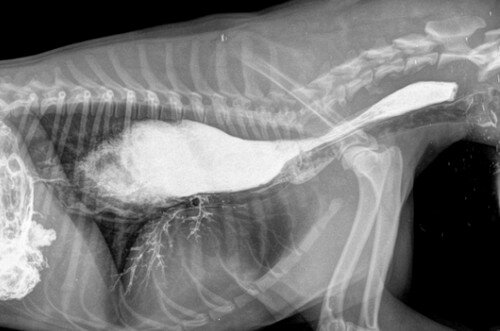

У девяти австралийских полицейских собак, которых кормили корм для собак производства Mars торговой марки Advance Dermocare - был диагностирован мегаэзофагус – болезнь характеризующаяся увеличение пищевода. Это заболевание вызывает гибель животных от голода. Корм, который должен перемещаться по пищеводу в желудок, вместо этого остается в пищеводе. Благодаря корму Mars (в РФ эта корпорация производит также корма для собак под торговыми наименованиями Pedigree, Chappi и другими), одна австралийская полицейская собака была подвергнута эвтаназии («гуманно» добита), вероятно, другие собаки будут иметь ту же участь.

В официальных новостях говорится, что эта патология «обычно не связана с кормом» - но на самом деле это не так. В последние годы мегаэзофагус был непосредственно связан с кормом для собак, в частности, из-за ингредиента под названием «мочевина», который, возможно, добавлялся в корм для домашних животных, чтобы увеличить его белковый анализ.